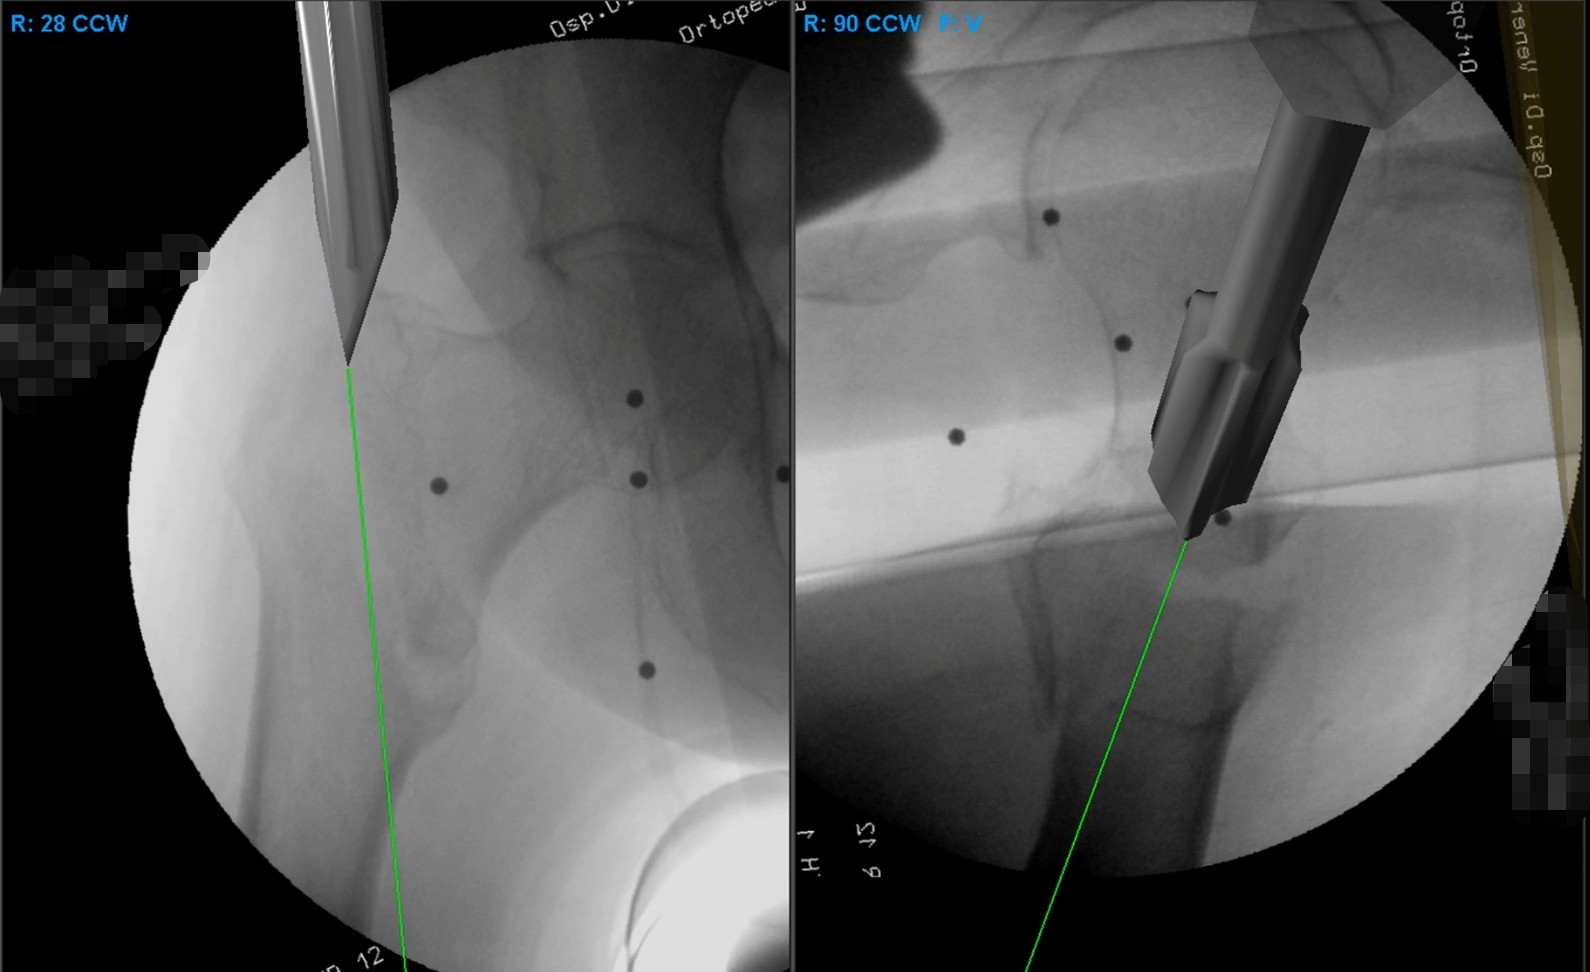

Trattare la frattura del femore utilizzando la realtà virtuale, preziosa “alleata” degli occhi e delle mani del chirurgo ortopedico. L’Ortopedia e Traumatologia dell’Ospedale “Di Venere” di Bari, con le prime 20 operazioni già eseguite con questo sistema tecnologico, ha varcato la nuova frontiera dell’innovazione applicata ad uno degli interventi preso a modello da Agenas per misurare la qualità […]